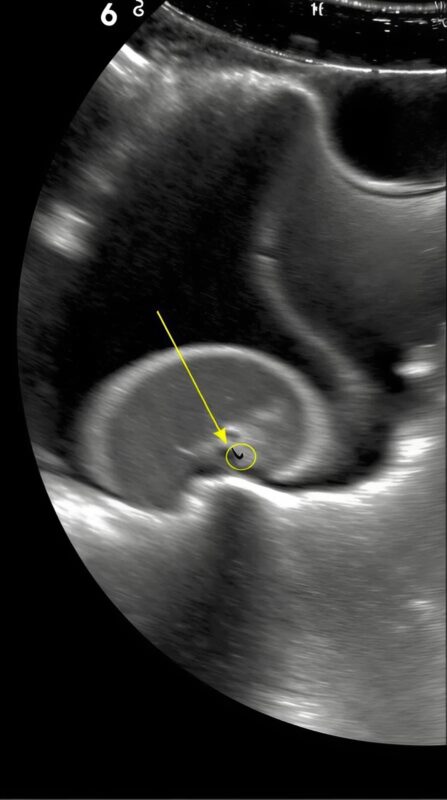

I blinked. Surgery? For stomach pain? My mind spun. Seeing my panic, he explained carefully. The scan revealed something small and dangerous inside her stomach. Something that shouldn’t be there. A pin.

I couldn’t process it. My daughter, my little girl, had swallowed a pin. My thoughts scattered. How? When? I replayed the day in my mind. She had been playing on the floor, surrounded by scattered buttons and threads. One careless moment—one blink—could have caused disaster.